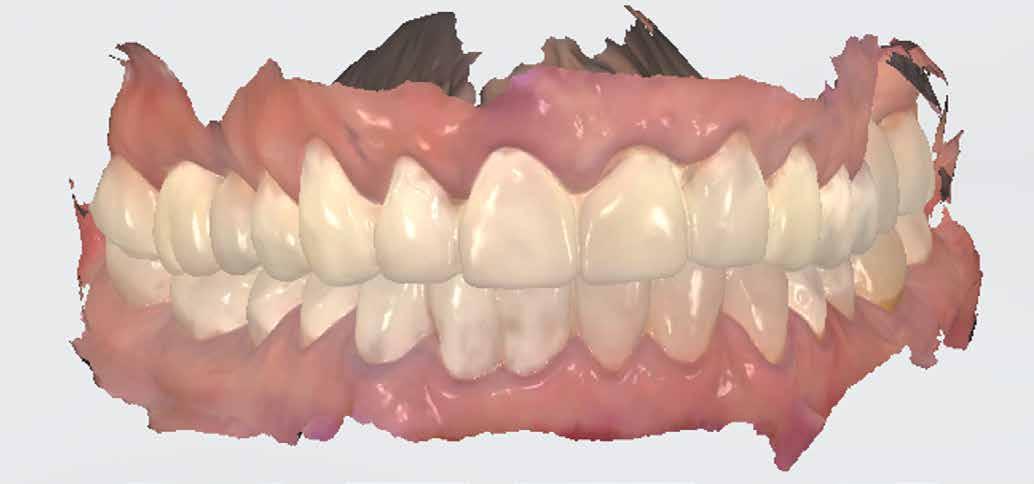

Az már egyértelművé vált, hogy a fogászati CAD/CAM, a folyamatos, gyors fejlődésének köszönhetően évről évre nagyobb részt fed le a kézműves, manuális fogtechnikai munkafolyamatok területén. A 3D nyomtatás fejlesztése, a szoftveres alkalmazások bővítése ma már lehetővé teszi digitálisan készített kivehető pótlások készítését. Teljes alsó-felső protézis vagy éppen fémlemez már kivitelezhető CAD/CAM technológiával. A fémlemezes részleges kivehető megoldások teljes digitális megoldásai még váratnak magukra, de ne legyenek illúzióink (1. kép).